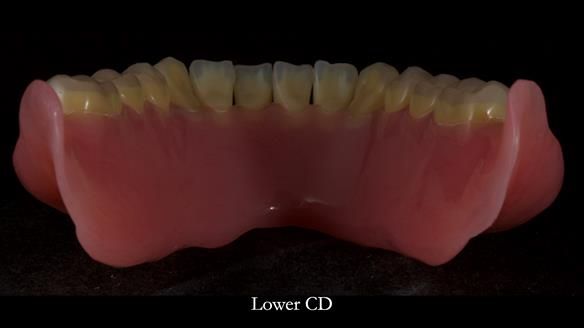

Welcome to Newsletter 83. This month I am sharing Sheila’s case — a very challenging but rewarding complete denture case. Sheila had flat ridges, a small mouth opening, a large tongue and had never been able to wear complete dentures of any kind. Everything was loose and sore. She felt embarrassed and looked older without dentures. She wanted a stable, comfortable result, and she wanted to avoid implants because she has taken bisphosphonates for more than five years.

Because her denture space anatomy was limited, I took two working impressions at the same visit. She had very little space in the lower jaw because of the spread of the tongue and the fact she had never worn a lower denture. This made it difficult to judge exactly where the borders needed to be and how much functional space we truly had.

In Sheila’s case, the Dr Abe shaped impression gave a more stable and comfortable result. Sheila preferred the shape produced by the Abe method, so that is the one we used for the registration rims, the trial denture and the final dentures. But making both impressions was worthwhile. It meant we had every option covered and could choose what worked best for her mouth.

In this newsletter I will take you through Sheila’s full protocol step by step — including impressions, French Impression Technique, Dr Abe shaping, copying Kirsty MacColl’s smile, the try-in, the final fit, and the copy dentures we made afterwards.